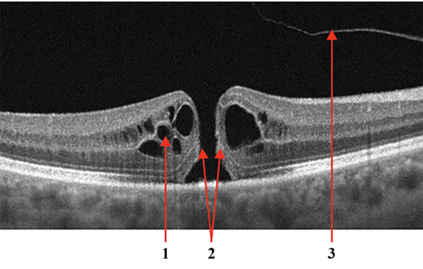

Optical coherence tomography (OCT) is a non-invasive imaging technique with extensive clinical applications in ophthalmology. OCT enables the visualization of the retinal layers, playing a vital role in the early detection and monitoring of retinal diseases. OCT uses the principle of light wave interference to create detailed images of the retinal microstructures, making it a valuable tool for diagnosing ocular conditions. This work presents an open-access OCT dataset (OCTDL) comprising over 1600 high-resolution OCT images labeled according to disease group and retinal pathology. The dataset consists of OCT records of patients with Age-related Macular Degeneration (AMD), Diabetic Macular Edema (DME), Epiretinal Membrane (ERM), Retinal Artery Occlusion (RAO), Retinal Vein Occlusion (RVO), and Vitreomacular Interface Disease (VID). The images were acquired with an Optovue Avanti RTVue XR using raster scanning protocols with dynamic scan length and image resolution. Each retinal b-scan was acquired by centering on the fovea and interpreted and cataloged by an experienced retinal specialist. In this work, we applied Deep Learning classification techniques to this new open-access dataset.